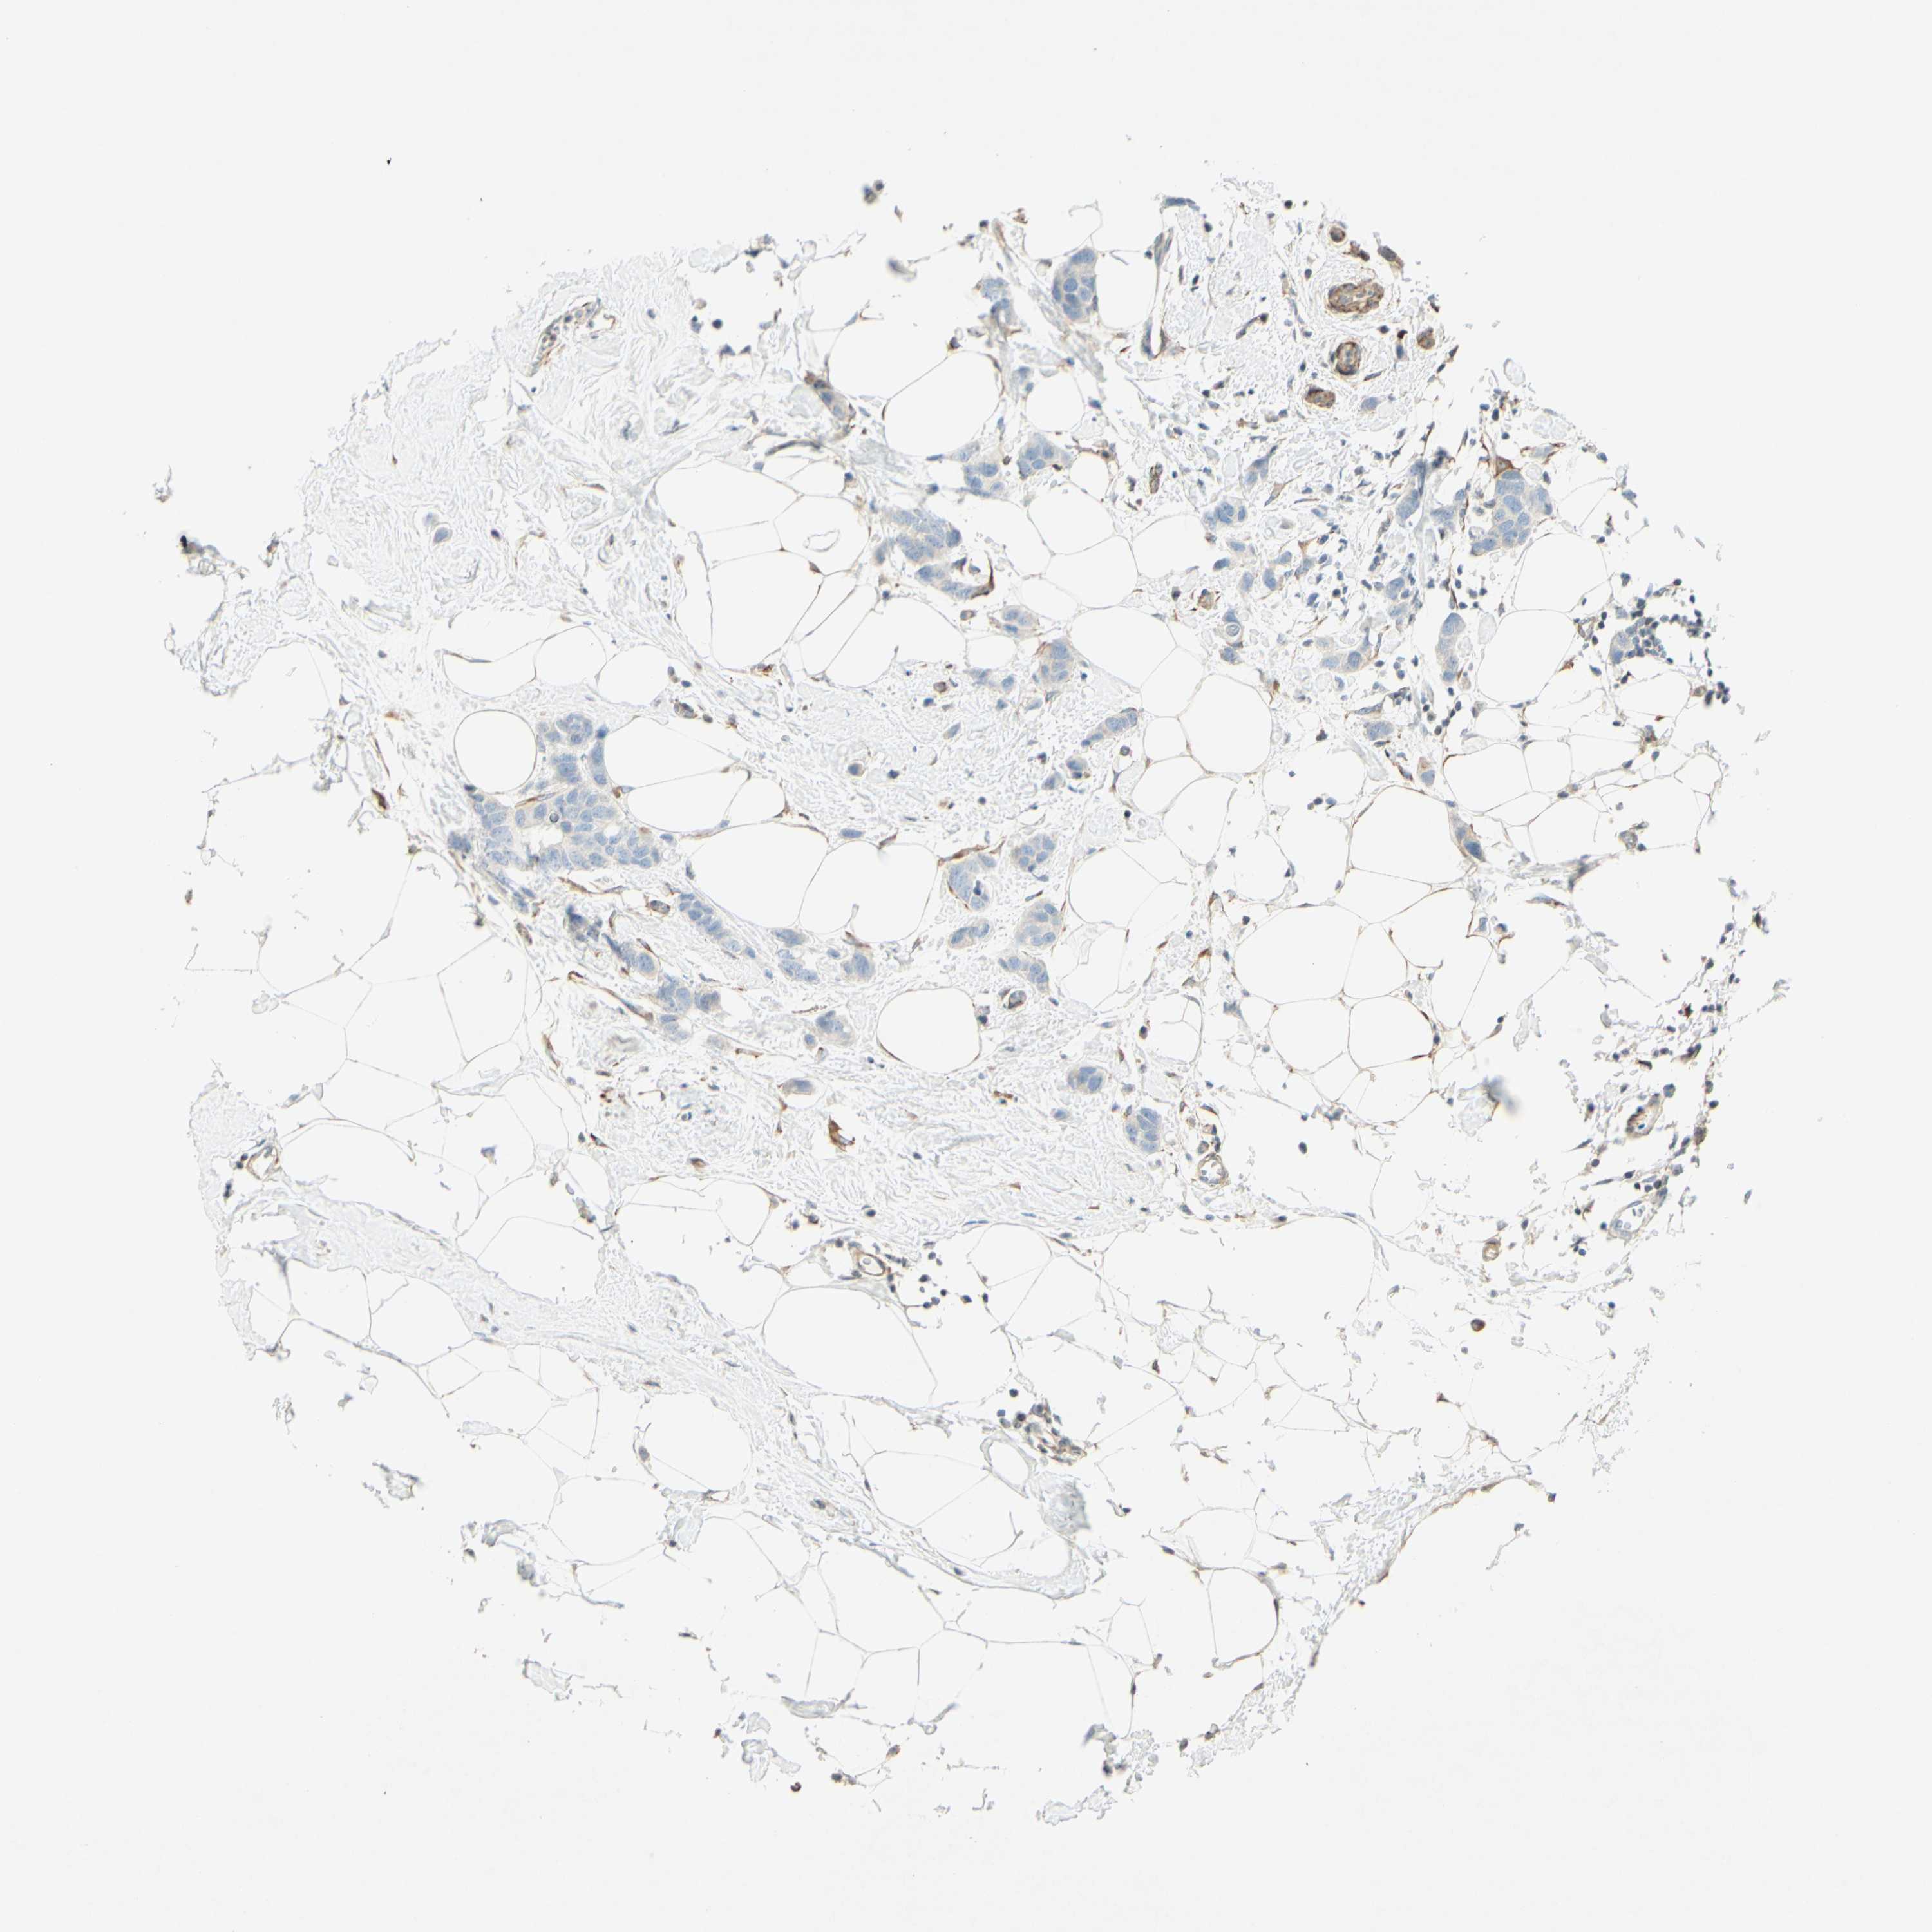

CANCER BREAST CANCER Show tissue menu

BRCA TCGA BRCA VALIDATION PROTEIN EXPRESSION

ANTIBODIES

AND

VALIDATION